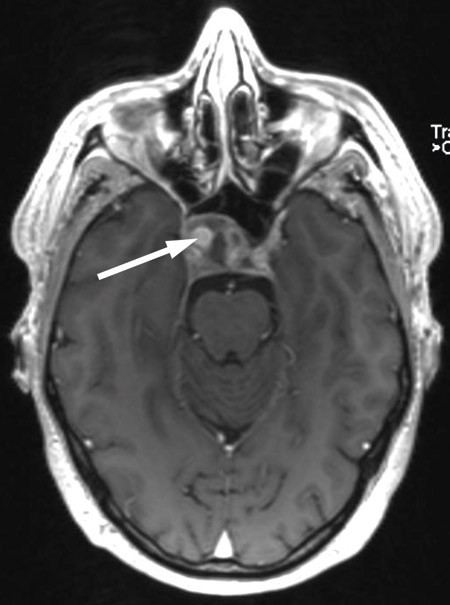

Cerebral CT og CT-angiografi like etter innleggelsen viste ikke tegn til blødning, men man fant på høyre side et intrakavernøst carotisaneurisme med diameter på 10 mm og en beineroderende prosess i sfenoidalsinus og clivus (fig 1, fig 2). MR-undersøkelse av hodet med og uten kontrast bekreftet et aneurisme i mediale del av sinus cavernosus på høyre side og beindestruksjon i samme område (fig 3).

MR-undersøkelsen og funnet av beindestruksjon ga mistanke om en kronisk sinusitt i sfenoidalsinus, og kombinasjonen av beindestruksjon og aneurisme kunne tyde på mulig aspergillusinfeksjon med mykotisk aneurisme på a. carotis interna i skallebasis. Beindestruksjon i sfenoidalsinus er forbundet med stor fare for ekstrem epistaxis, og vi kjenner til dødsfall som følge av epistaxis via sfenoidalsinus fra et tilsvarende aneurisme.